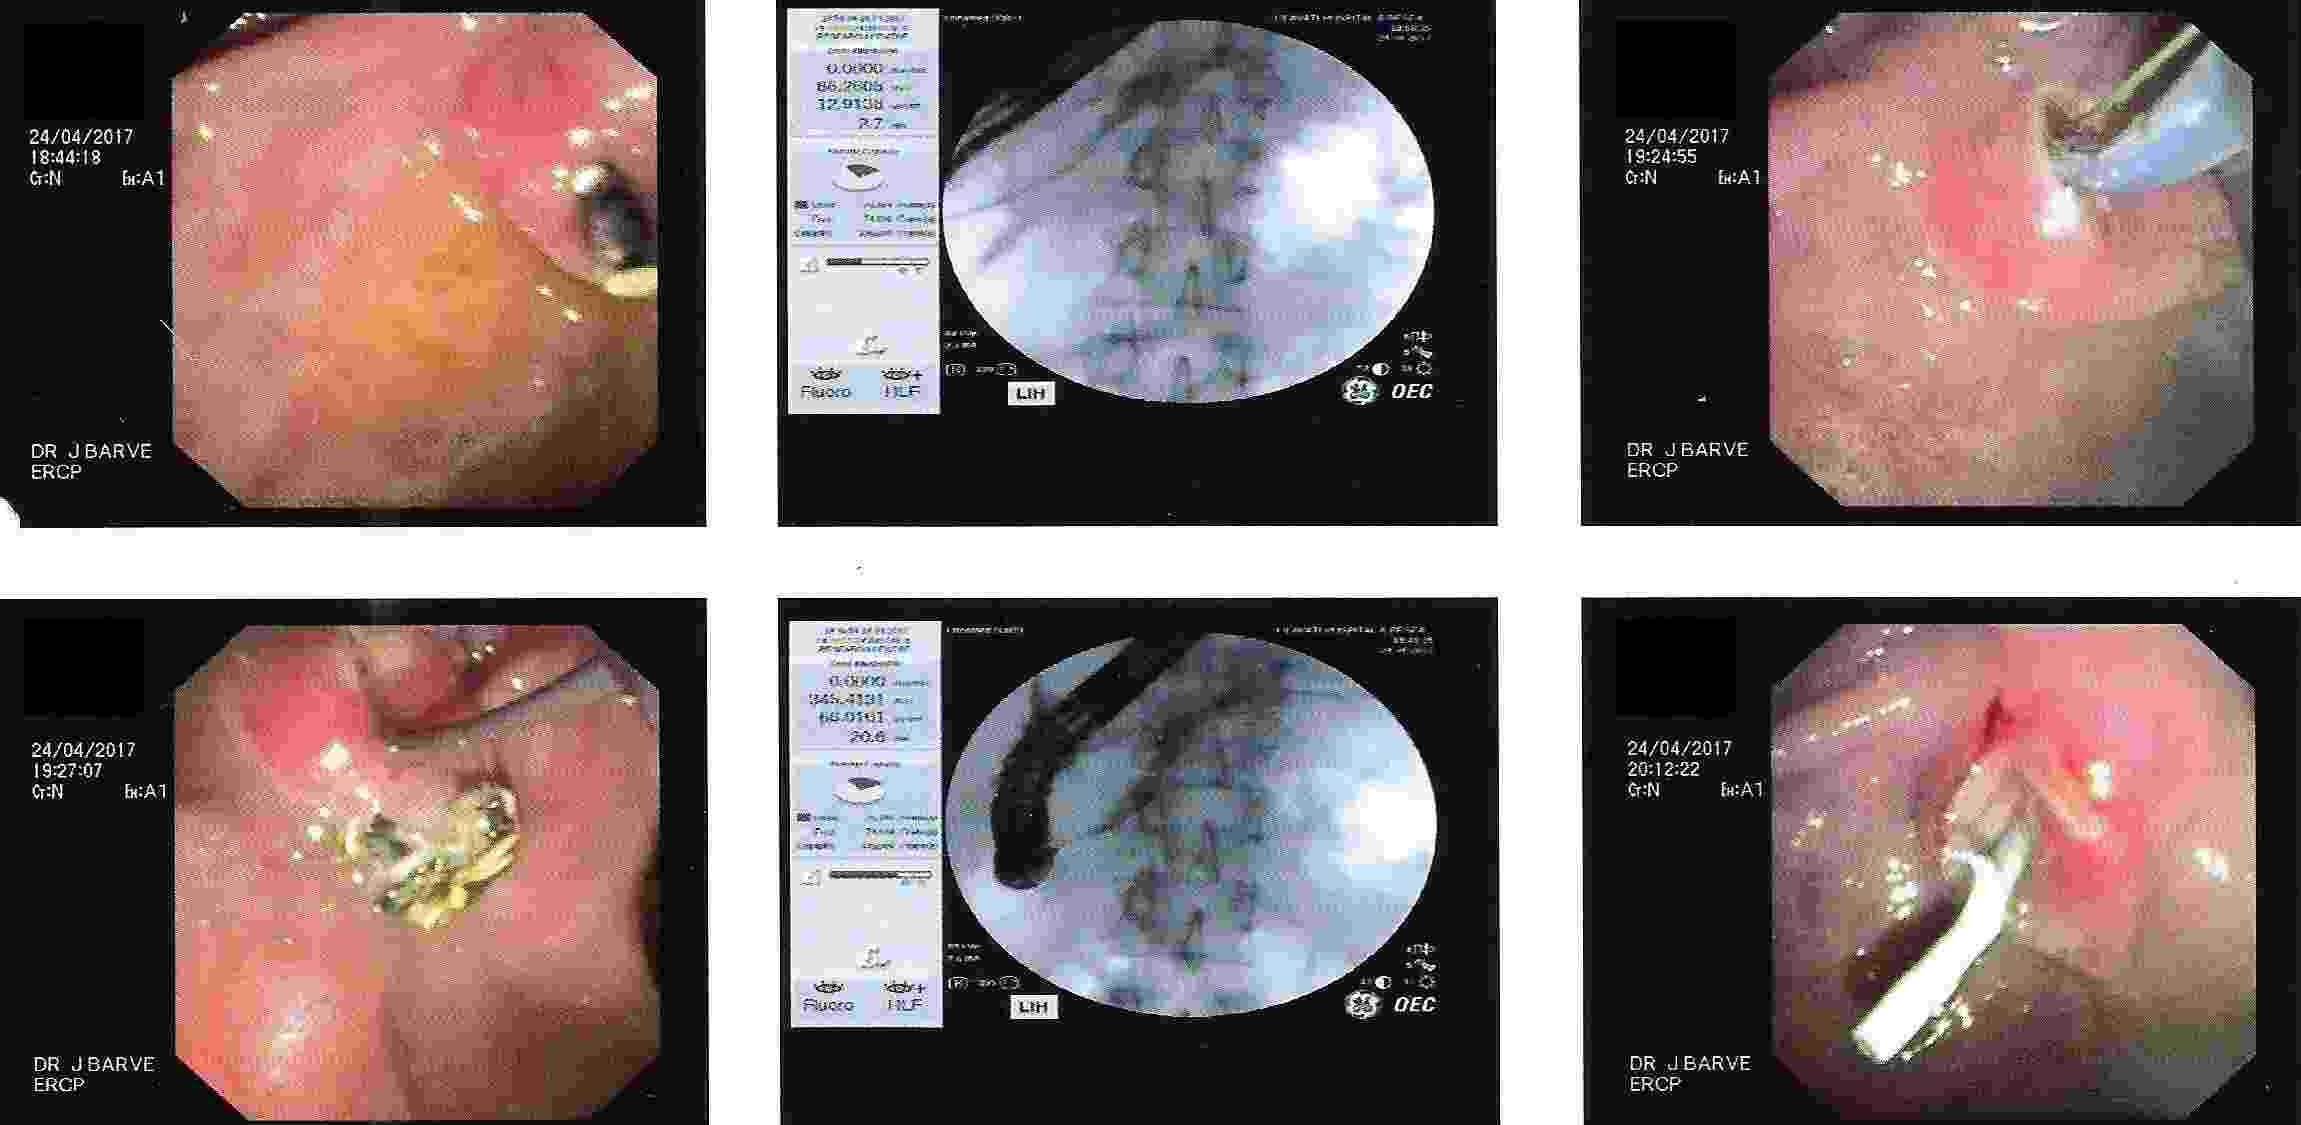

Endoscopic Retrograde Cholangio Pancreatography is an advanced endoscopic procedure related to

diseases of pancreas and biliary tree. Common indication for ERCP is jaundice due to obstruction

of biliary tube, which drains the bile from the liver into the intestine.

Obstruction can be due to a gallstone, which has slipped into bile tube and has blocked the bile tube.

These Stones can be removed by ERCP, without any surgery being involved.

Common Biles Duct Stones

Common Biles Duct Stones

Impacted Stone in Common Bile Duct